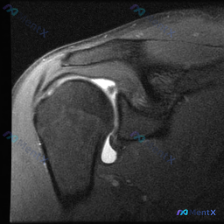

整理了一个肩关节MRI-T2序列冠状位的病例讨论材料,医生提问关注盂唇病变,但影像最突出的是冈上肌腱全层撕裂。这份病例的核心疑问点和影像发现存在一定不匹配,大家第一眼怎么看?

整理了一份有意思的肩关节MRI读片病例,问题一开始聚焦在「软组织积液」上,但梳理下来发现这个病例很容易踩坑,分享一下我的思路。 一、影像基本信息 这是一份肩关节冠状位T2序列MRI,我们按结构逐层看一下观察到的征象: 1. 冈上肌腱:肱骨大结节止点处可见条带状局灶异常高信号,贯穿肌腱全层,从关节面延...

整理了一份肩关节MRI的病例资料,临床申请的检查目的是排查盂唇病变,不过仔细阅片后发现核心异常好像不在盂唇那边? 先放已明确的影像基础信息: - 序列修正:初始标注为T1序列,实际影像符合质子密度压脂(PD FS)或T2压脂序列特征,对积液、肌腱损伤敏感 - 核心可见表现:肱骨大结节处肌腱信号异常、...

看到一个肩关节MRI影像分析的病例材料,影像为冠状位T2加权图像,主要发现如下: 1. 冈上肌腱远端附着处全层撕裂,T2序列显示高信号液体填充 2. 肩峰下-三角肌下滑囊内有明显积液 3. 盂肱关节腔内有显著液体潴留 用户的核心问题是关于「盂唇病变」的可能性。这个病例有几个点值得讨论: - 冈上肌腱...